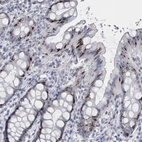

Immunohistochemical staining of human rectum shows strong cytoplasmic positivity in a subset of goblet cells.